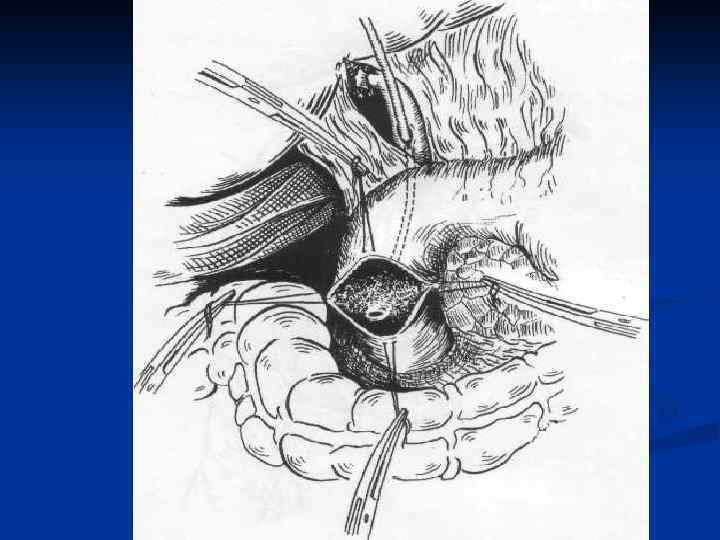

I. Восстановительные операции (восстановление проходимости протоков) 1. Эндобилиарные вмешательства под УЗИ или R – контролем (бужирование, баллонная дилатация, стентирование протоков). 2. Пластика стриктуры 3. Иссечение стриктуры с наложением анастомоза. II. Реконструктивные операции (наложение билиодигестивных анастомозов) 1. Анастомозы внепеченочных желчных протоков: а) с двенадцатиперстной кишкой (ХДА) б) с тощей кишкой (гепатико-, холедохоеюноанастомозы по Ру или по Брауну). 2. Анастомозы внутрипеченочных желчных протоков с сегментом тощей кишки, выключенной по Ру или желудком при высоких стриктурах

I. Восстановительные операции (восстановление проходимости протоков) 1. Эндобилиарные вмешательства под УЗИ или R – контролем (бужирование, баллонная дилатация, стентирование протоков). 2. Пластика стриктуры 3. Иссечение стриктуры с наложением анастомоза. II. Реконструктивные операции (наложение билиодигестивных анастомозов) 1. Анастомозы внепеченочных желчных протоков: а) с двенадцатиперстной кишкой (ХДА) б) с тощей кишкой (гепатико-, холедохоеюноанастомозы по Ру или по Брауну). 2. Анастомозы внутрипеченочных желчных протоков с сегментом тощей кишки, выключенной по Ру или желудком при высоких стриктурах